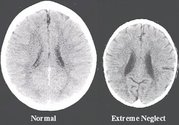

ABD’deki Washington Üniversitesi tarafından yapılan araştırmaya göre sevgiyle büyüyen çocukların beyni daha çok gelişiyor. Nörologların beyin gelişimini incelemek için yaptıkları araştırma bilim insanlarını hayrete düşürdü. Yapılan araştırmaya göre 3 yaşında iki kız çocuğuna ait olan beyinlerin gelişimi yaşam şekillerine göre farklılık gösteriyor.

Ailesi tarafından ihmal edilen ve ilgisiz bırakılan kız çocuğunun beyni az gelişirken, ailesi tarafından ilgi gösterilen ve sevgi beslenen kız çocuğunun beyninin diğerine göre daha gelişmiş olduğu tespit edildi.

Yukarıda sağdaki beyne sahip çocuğun daha az zeki, daha az sosyal, suça ve kötü bağımlılıklara daha yatkın şekilde büyüyeceği iddia ediliyor. Ayrıca sağdaki beyne sahip çocuğun ileride işsiz kalmaya ve refahtan uzak yaşamaya daha meyilli olacağı belirtiliyor. Bu araştırma sonucunda sevgisizliğin beynin gelişimini engellediği ortaya çıktı.